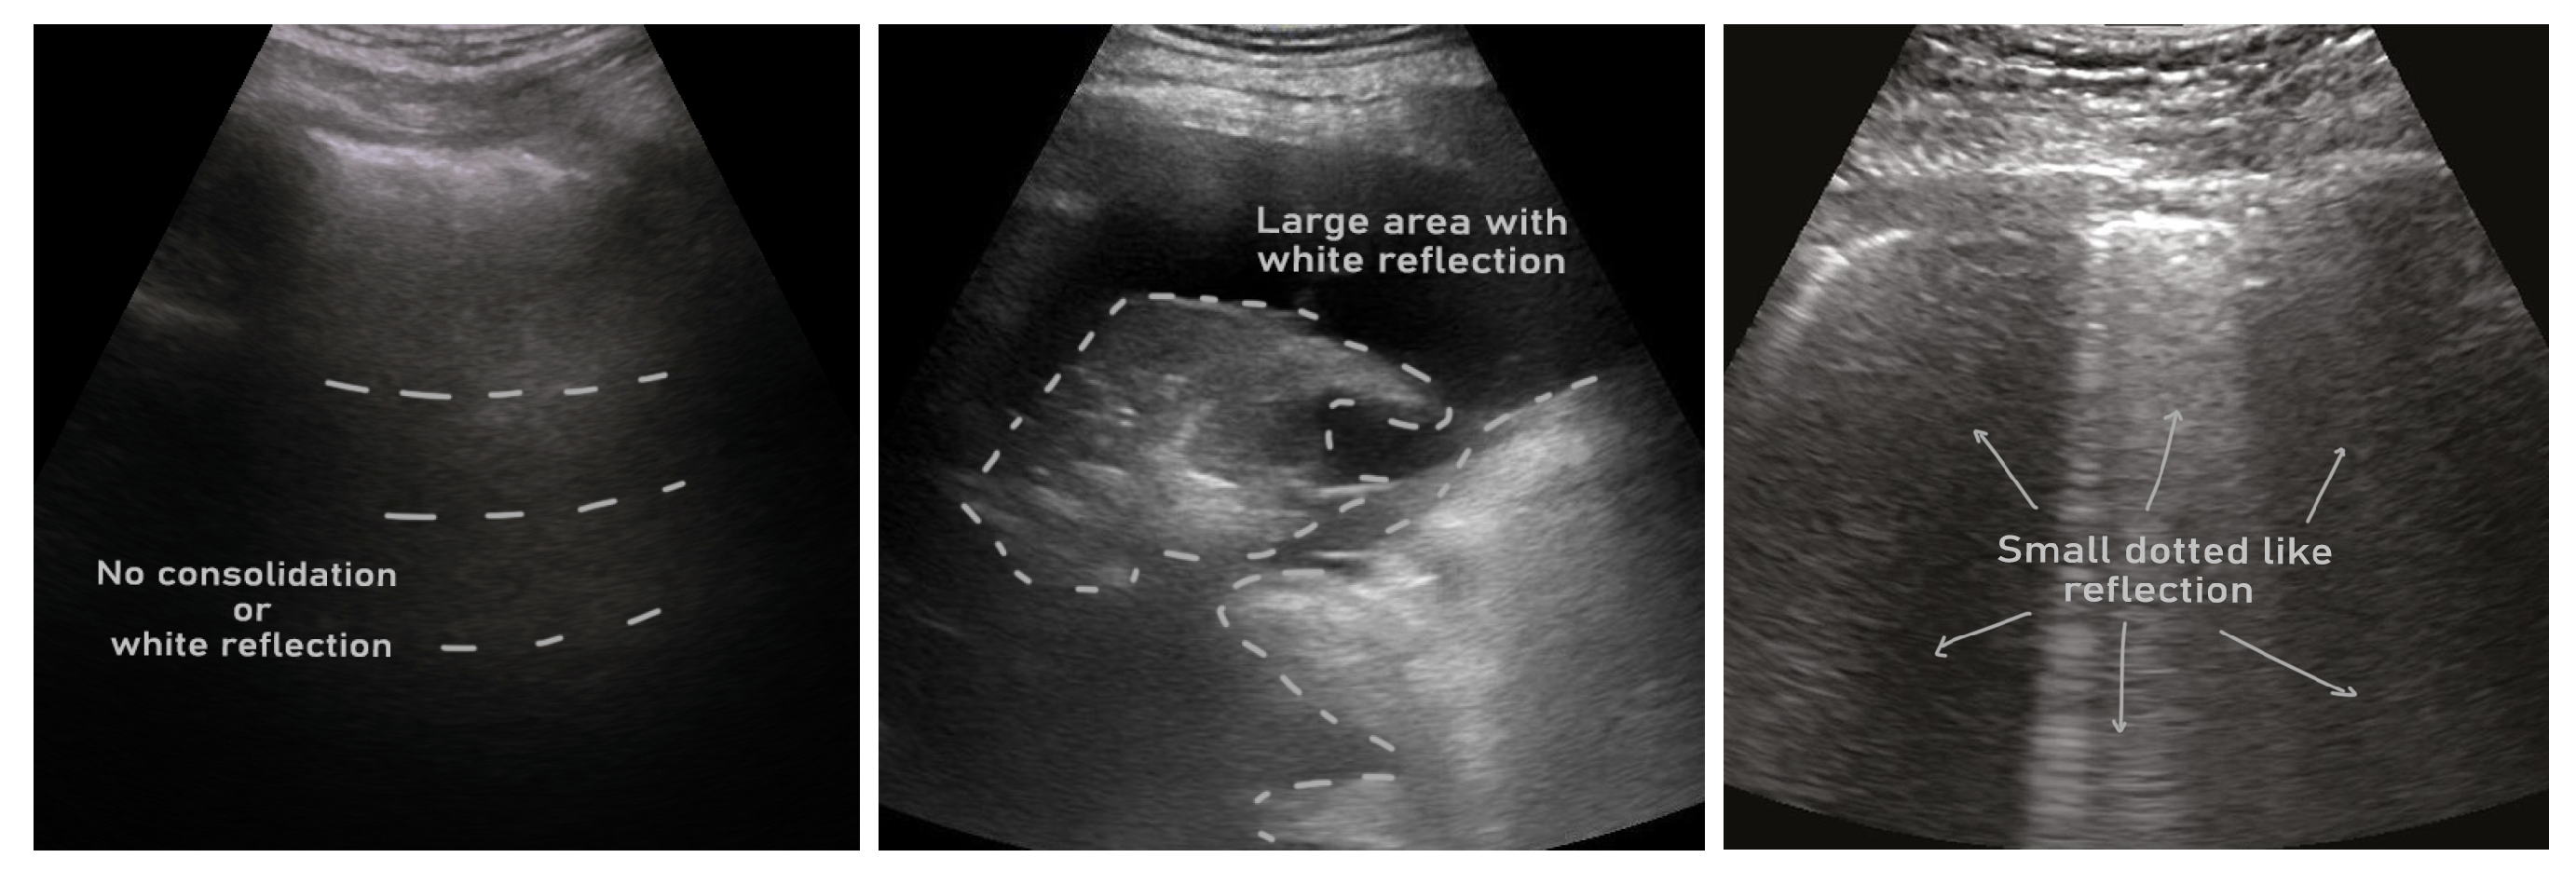

- Soldati, G.; Demi, M.; Smargiassi, A.; Inchingolo, R.; Demi, L. The role of ultrasound lung artifacts in the diagnosis of respiratory diseases. Expert Rev. Respir. Med. 2019, 13, 163–172. [Google Scholar] [CrossRef]

- Soldati, G.; Smargiassi, A.; Inchingolo, R.; Buonsenso, D.; Perrone, T.; Briganti, D.F.; Perlini, S.; Torri, E.; Mariani, A.; Mossolani, E.E.; others. Proposal for international standardization of the use of lung ultrasound for patients with COVID-19: A simple, quantitative, reproducible method. J. Ultrasound Med. 2020, 39, 1413–1419. [Google Scholar] [CrossRef] [PubMed]